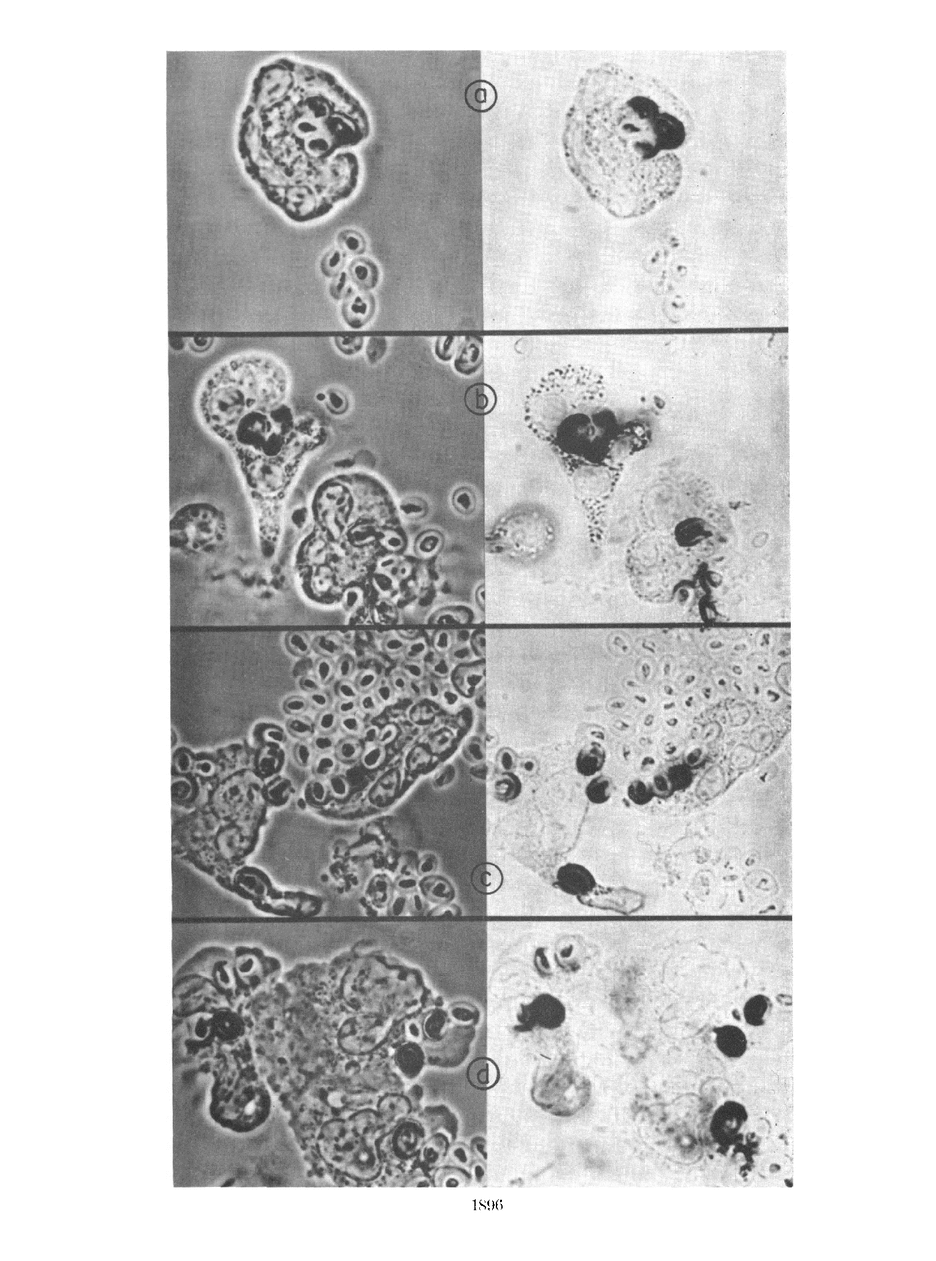

The leukocytes of patients with chronic granulomatous disease (CGD) may be identified by their failure to reduce Nitro Blue Tetrazolium (NBT) during phagocytosis. This reaction, normally detected in the phagocytic vacuole, is absent or delayed in CGD monocytes and eosinophils as well as in neutrophils, even though sonicates of normal and CGD leukocytes contain equal activities of a cyanide insensitive enzyme system capable of reduction of NBT in the presence of pyridine nucleotide.